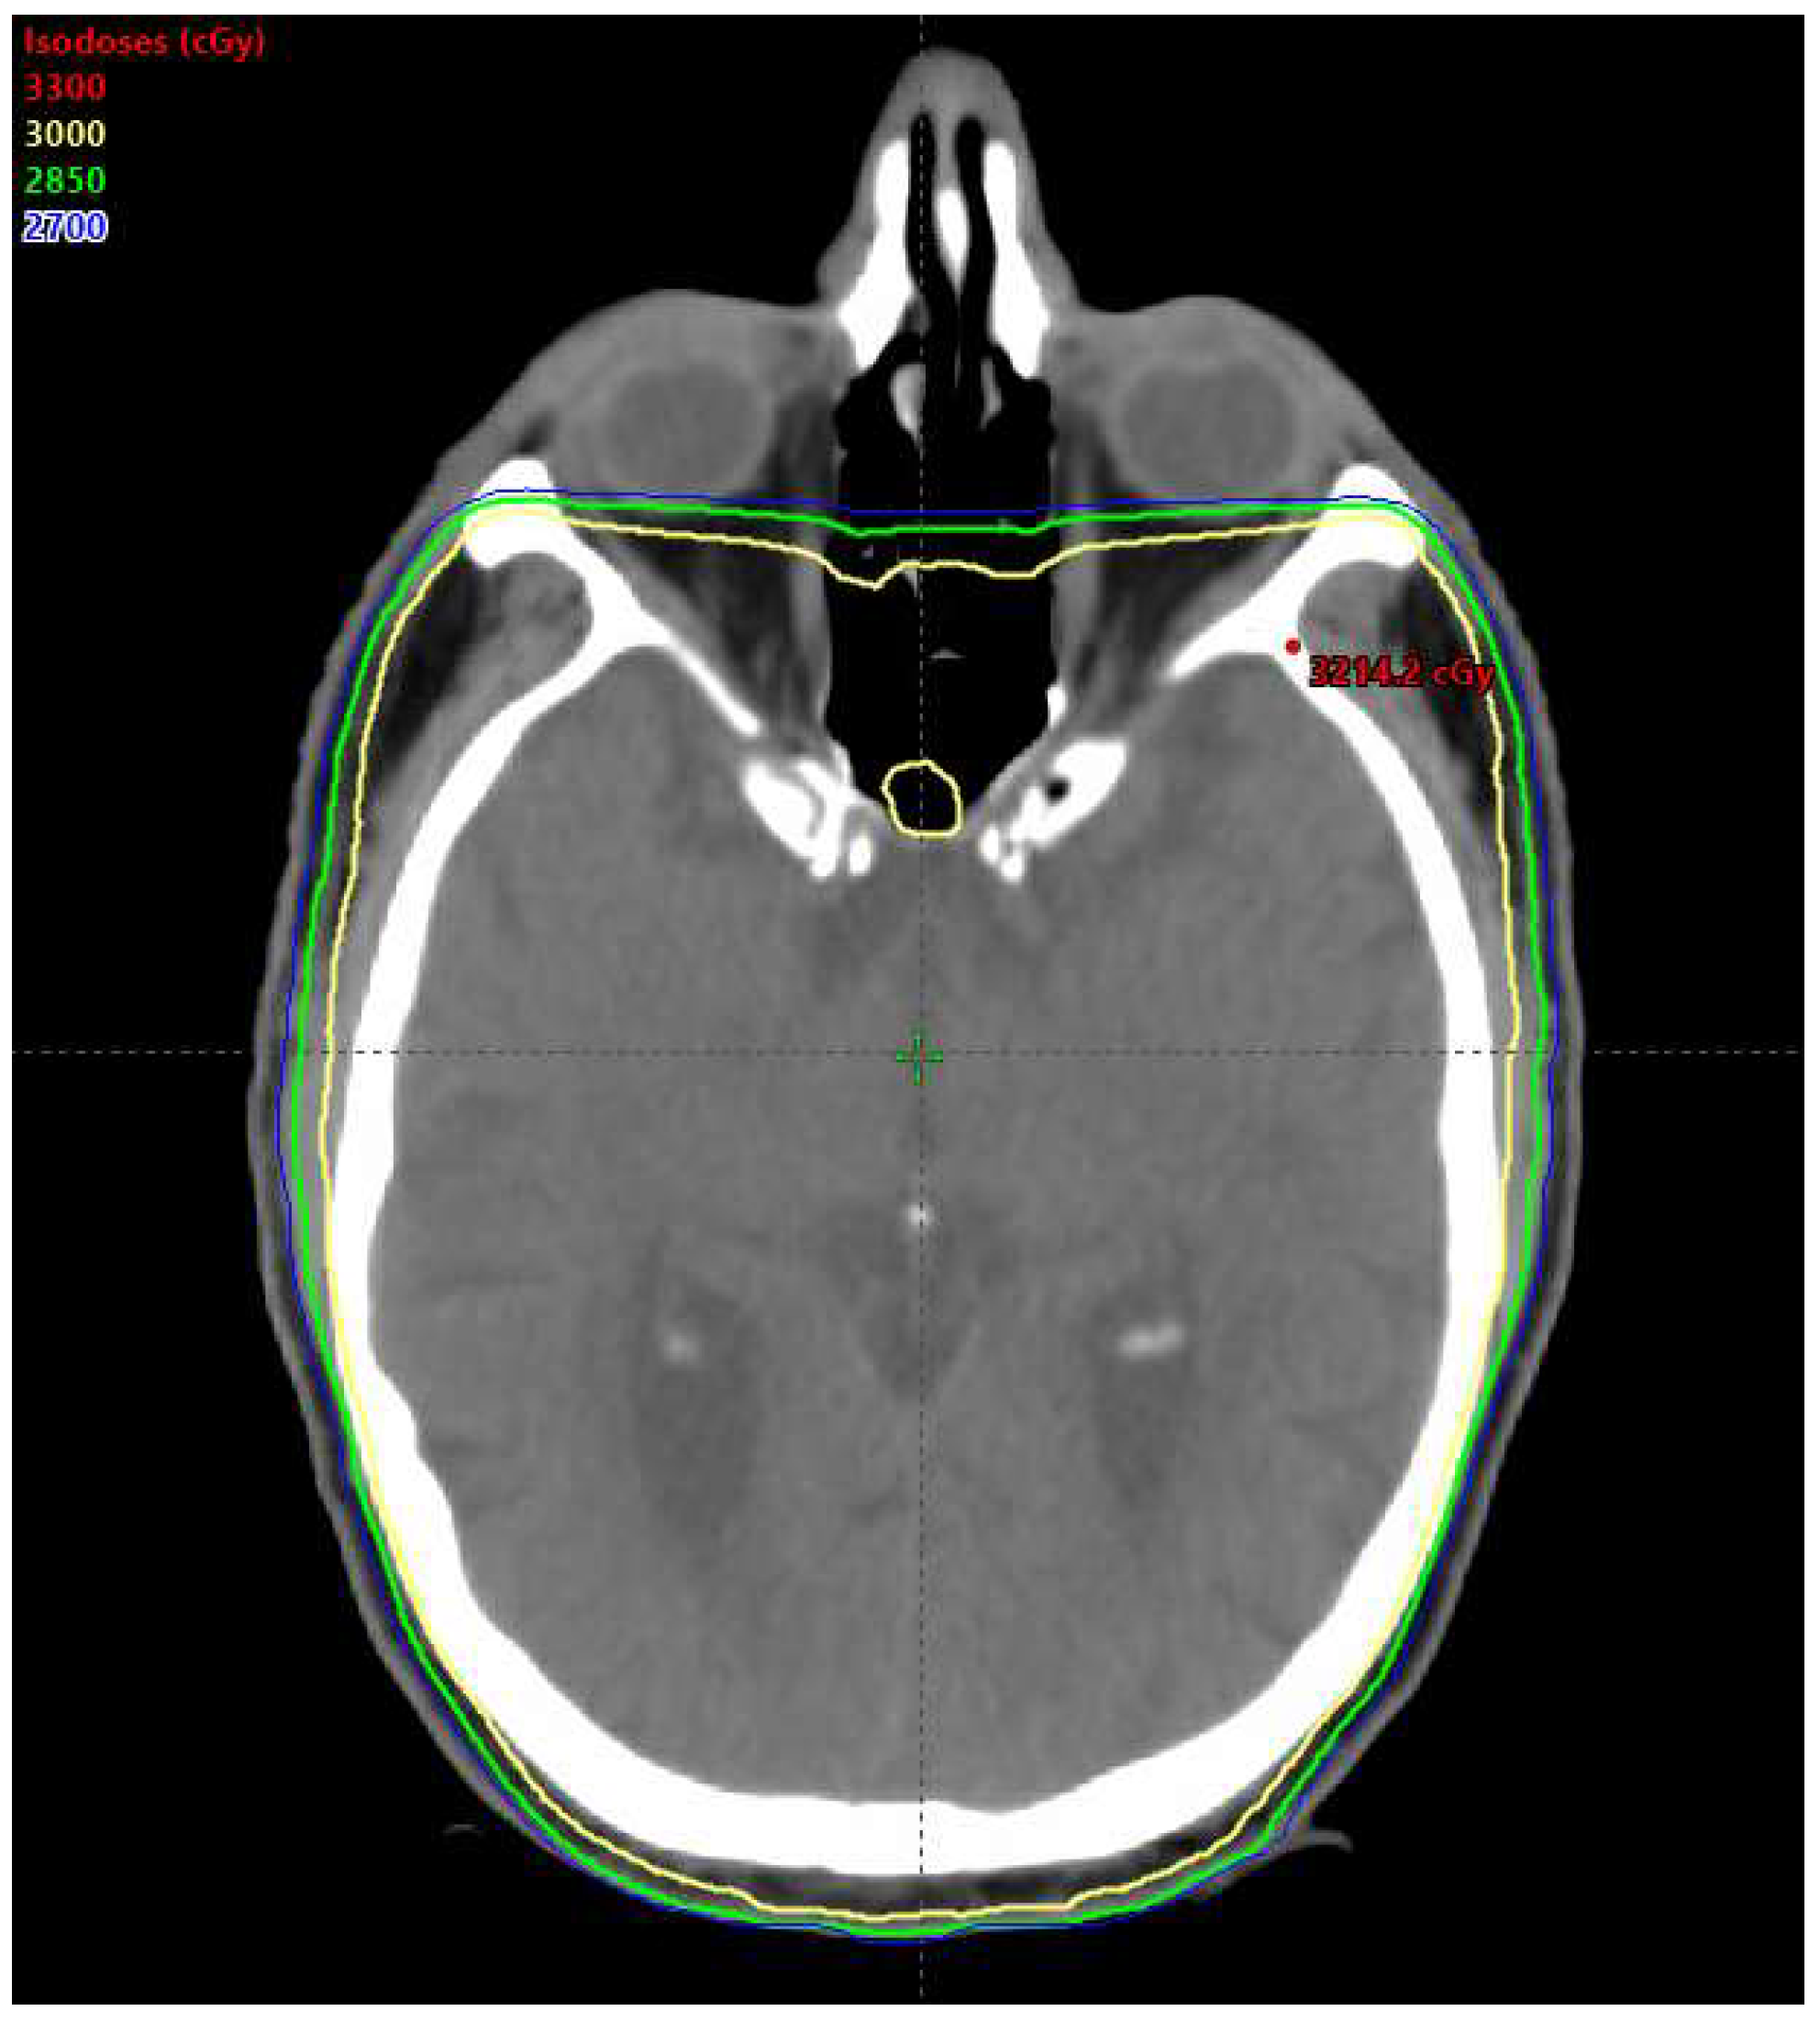

3. Stereotactic Radiosurgery